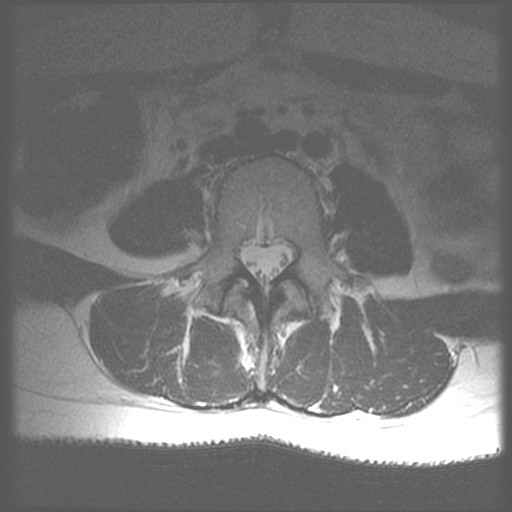

Centrale Wervel Zuil

Lage Wervel Zuil